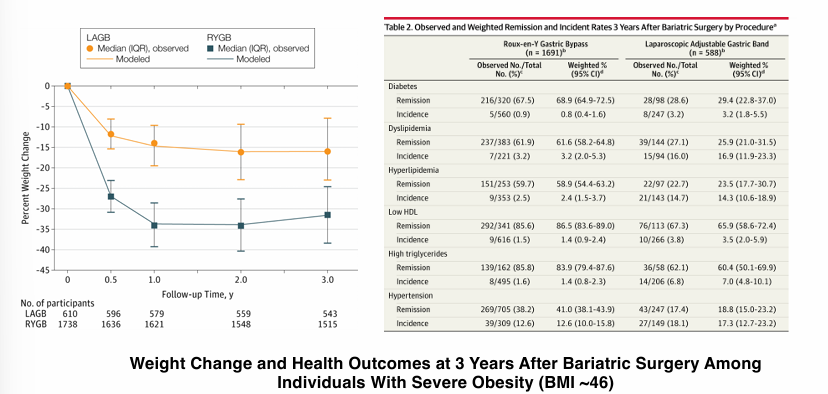

environmental causes of hypertension- obesity